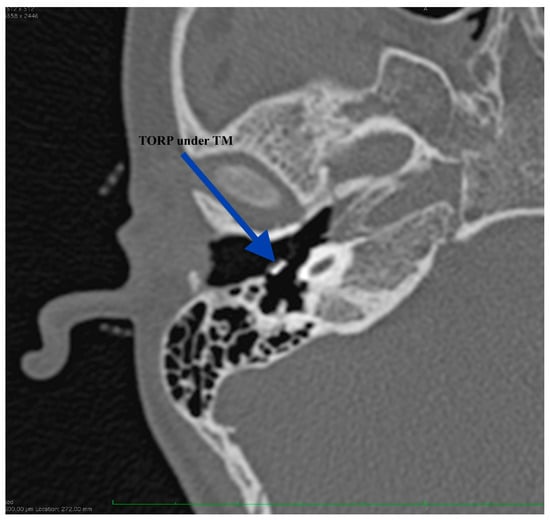

The patient reported immediate postoperative good hearing but failed to present at our Department for performing an audiogram. His hearing was firstly evaluated at 2 months after right ear surgery demonstrating an air-bone gap of 41.6 dB (from 56.6 dB preoperatively). We could not explain at that moment the results but, at 9 months after surgery we were able to have another CT scan performed. The imaging showed good positioning of the ossicular prosthesis (Figure 10 and Figure 11). Without surgical investigation of the middle ear is it impossible to know the precise reason why the hearing restoration is not as good as we expected. We can hypothesize about local healing changes but we cannot be sure.

Figure 11.

CT scan at 9 months after surgery, showing proper positioning of the prosthesis: TORP shoe in the cochleostomy.